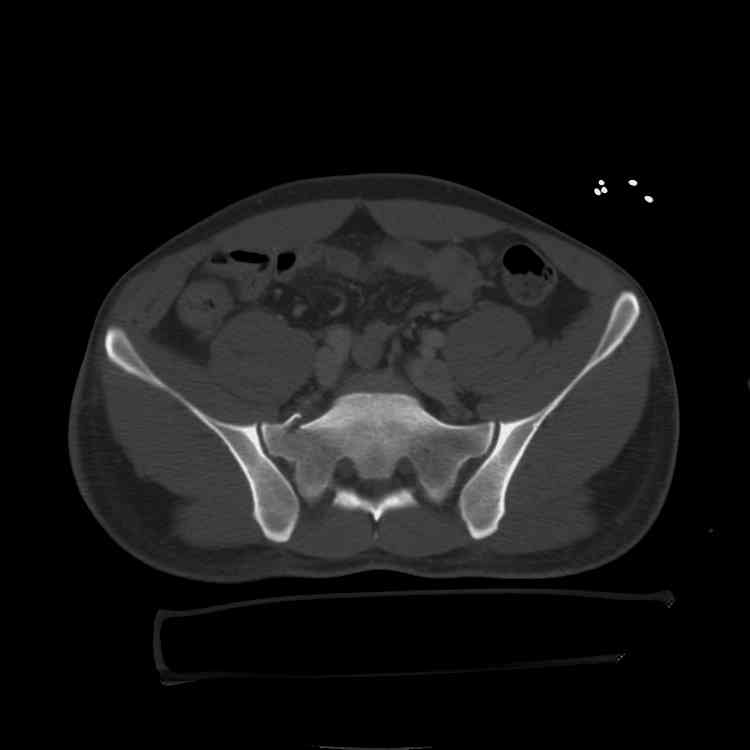

hello,this is a healthy 22yo male. peds vs auto.

no other injuries. has anyone treated these non-operatively? thanks.

It's type A pelvic-ring lesions. Because

the pelvic ring is stable, it

cannot be displaced by physiologic

forces and may be treated non-operativly in male.

One bit of important yet omitted info is the patient's physical exam... if this pelvic ring injury is unstable to exam, then I'd recommend operative reduction and stable fixation to him.